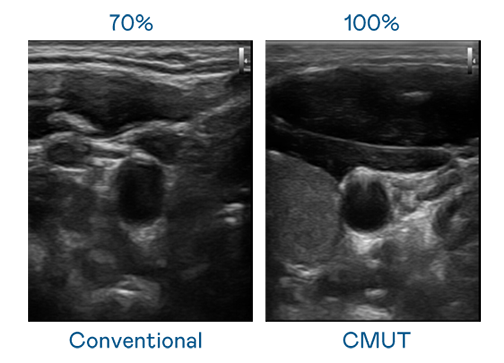

CMUT 技术是一种用电容式微机电元件来产生超音波讯号的技术。与传统 PZT 压电式技术相比,CMUT 频宽增加 30%,更宽频的超音波讯号让影像解析度大幅提升,是实现高影像品质医疗超音波扫描、促进精准医疗发展的关键技术。

大频宽带来超清晰影像

超音波影像的解析度高低,首先取决于探头能发出的讯号频宽。w66利来 CMUT 可提供高清晰的超音波讯号,提供高频宽、高灵敏度、影像纹理细节更高的超音波影像,协助医护人员缩短影像判读时间及利用精准的医疗影像进行诊断。